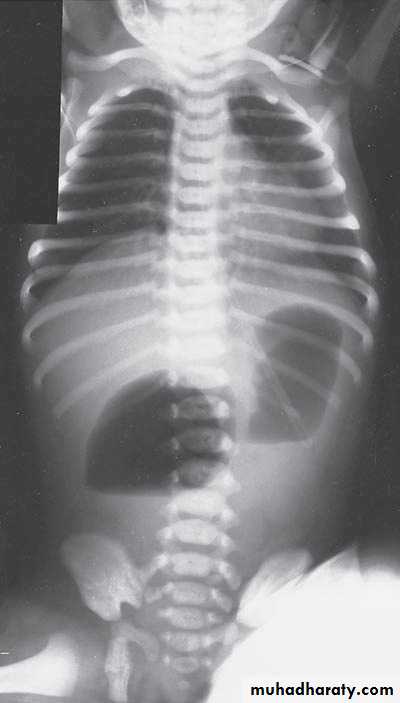

Oesophageal Atresia and Tracheo-Oesophageal Fistula,

First photo:

Diagnosis: pure atresiaDescription: radiolucent abdomen (no gases) + failure of nasogastric tube passage.

Second photo:

Diagnosis: TEF (with fistula)

Description: pass of gases to the abdomen + failure of nasogastric tube passage.

Diagnosis: TEF (atresia with fistula)

Benefits of X-ray:1- to see the failure of nasogastric tube passage.

2- to determine the type of TEF

3- to check the condition of the lung

4- diagnose the associated anomalies (aortic arch – vertebra – ribs)

5- to measure the length of the defect (1-2-3 cm or more)